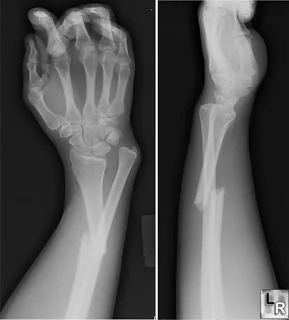

Colle’s Fracture

- Extra-articular fracture of the distal radius with dorsal and radial displacement of the wrist “Dinner fork” deformity

- Seen in elderly with osteoporosis

- Caused by falling on the outstretched hand

Treatment

- Undisplaced : Cast alone

- Displaced: (Sedation/ UGA / ULA), closed reduction, casting Wrist immobilized in flexion & ulnar deviation